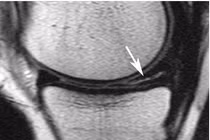

(khoahocdoisong.vn) - Sụn chêm hoạt động như một giảm sốc, hấp thu và truyền lực đều từ lồi cầu xương đùi xuống xương chày, làm giảm sang chấn cho sụn khớp. Sụn chêm góp phần tạo nên sự vững chắc cho khớp gối.